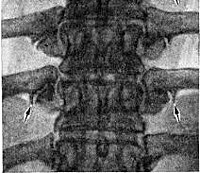

Для подтверждения диагноза выполняют рентгенографию поясничного отдела позвоночника. При спондилоартрозе обнаруживается сужение суставных щелей, более выраженное в нижней части поясничного отдела, субхондральный склероз и остеофиты по краям фасеточных суставов. Могут также выявляться суставные эрозии, кисты и подвывихи суставов. Для оценки вовлеченности мягких тканей и степени их компрессии при необходимости назначают МРТ позвоночника. При наличии неврологических симптомов (обычно наблюдаются при сочетании спондилоартроза с другими дистрофическими заболеваниями позвоночника) больного направляют на консультацию к неврологу.